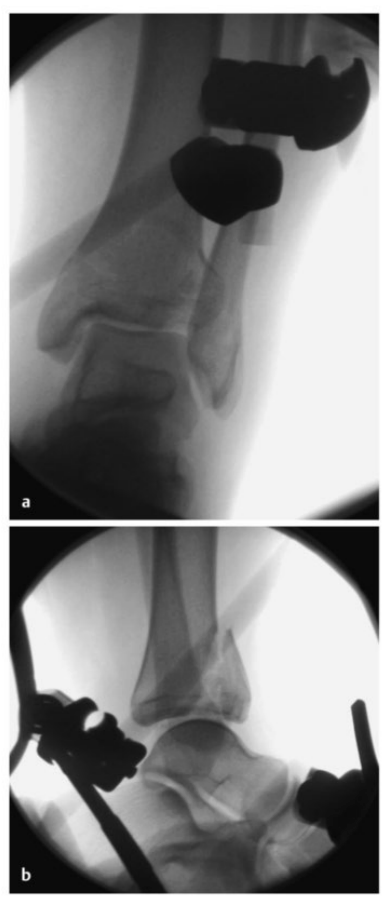

病例1在受伤后送往医院急诊,首先进行了跨踝关节外固定架。尽管患者初始存在Ⅱ度闭合性软组织损伤,但由于及时进行了复位并植入外固定架,未需实施筋膜间室切开术。在术前CT图像中,可清晰观察到3个主要骨折块及1个中央粉碎区。通过及时植入外固定架,可恢复关节位置,并有效避免软组织损伤进一步加重。

待软组织状况改善(出现 “皮肤皱纹征”)后,开始对患者进行手术治疗,首先处理腓骨(遵循 “先处理腓骨” 原则)。术中检查发现韧带联合存在不稳定情况。

术中三维CT 扫描确认骨折达到解剖复位,内植物位置良好。术后影像学检查证实骨折解剖复位,内植物位置正常。患者术后恢复过程顺利,关节功能恢复良好。